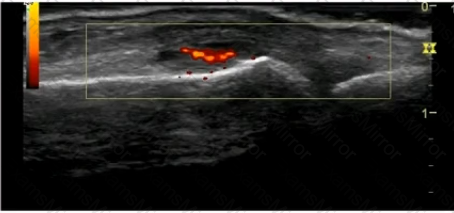

A 37-year-old female with a history of rheumatoid arthritis presents for sonographic evaluation. She has been in clinical remission for six months and is considering discontinuation of her biologic agent. Sonography of the right third metacarpophalangeal joint is shown. Which of the following is the MOST accurate description regarding this image?